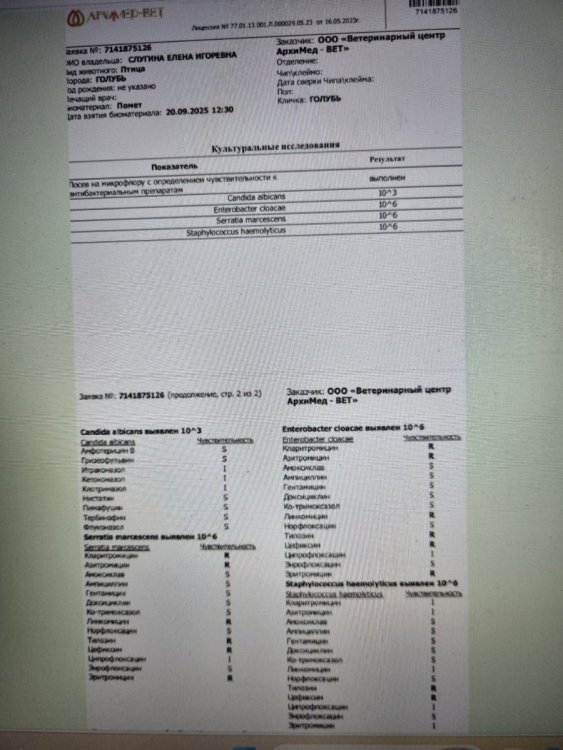

Это не у меня только так, вот люди в соседней теме сдавали параллельно в двух лабораториях, в одной лаборатории есть чувствительность к доксициклину, в другой нет